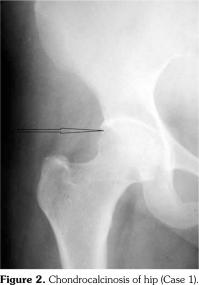

On examination, there was swelling and painful restriction of movement in her right knee. Imaging revealed calcification of cartilage of wrists, knee joints and hip joints although no microscopic confirmation was possible at this stage (Figure 1-4). She was investigated for a possible cause for CC, although investigations to screen for a metabolic cause turned out to be negative with a possibility for hereditary CC.

Case 2- A 39-year-old male patient presented with swelling of both knee joints. He also gave a history of recurrent painful swelling of knee joints and wrist joints for more than 10 years and was treated by an Ayurvedic physician. Other medical history or family history of medical problems were insignificant. There was a massive swelling of both knee joints with effusions, which was aspirated and the X-rays revealed calcification of the articular cartilages (Figure 5). A written informed consent was obtained from the patient.